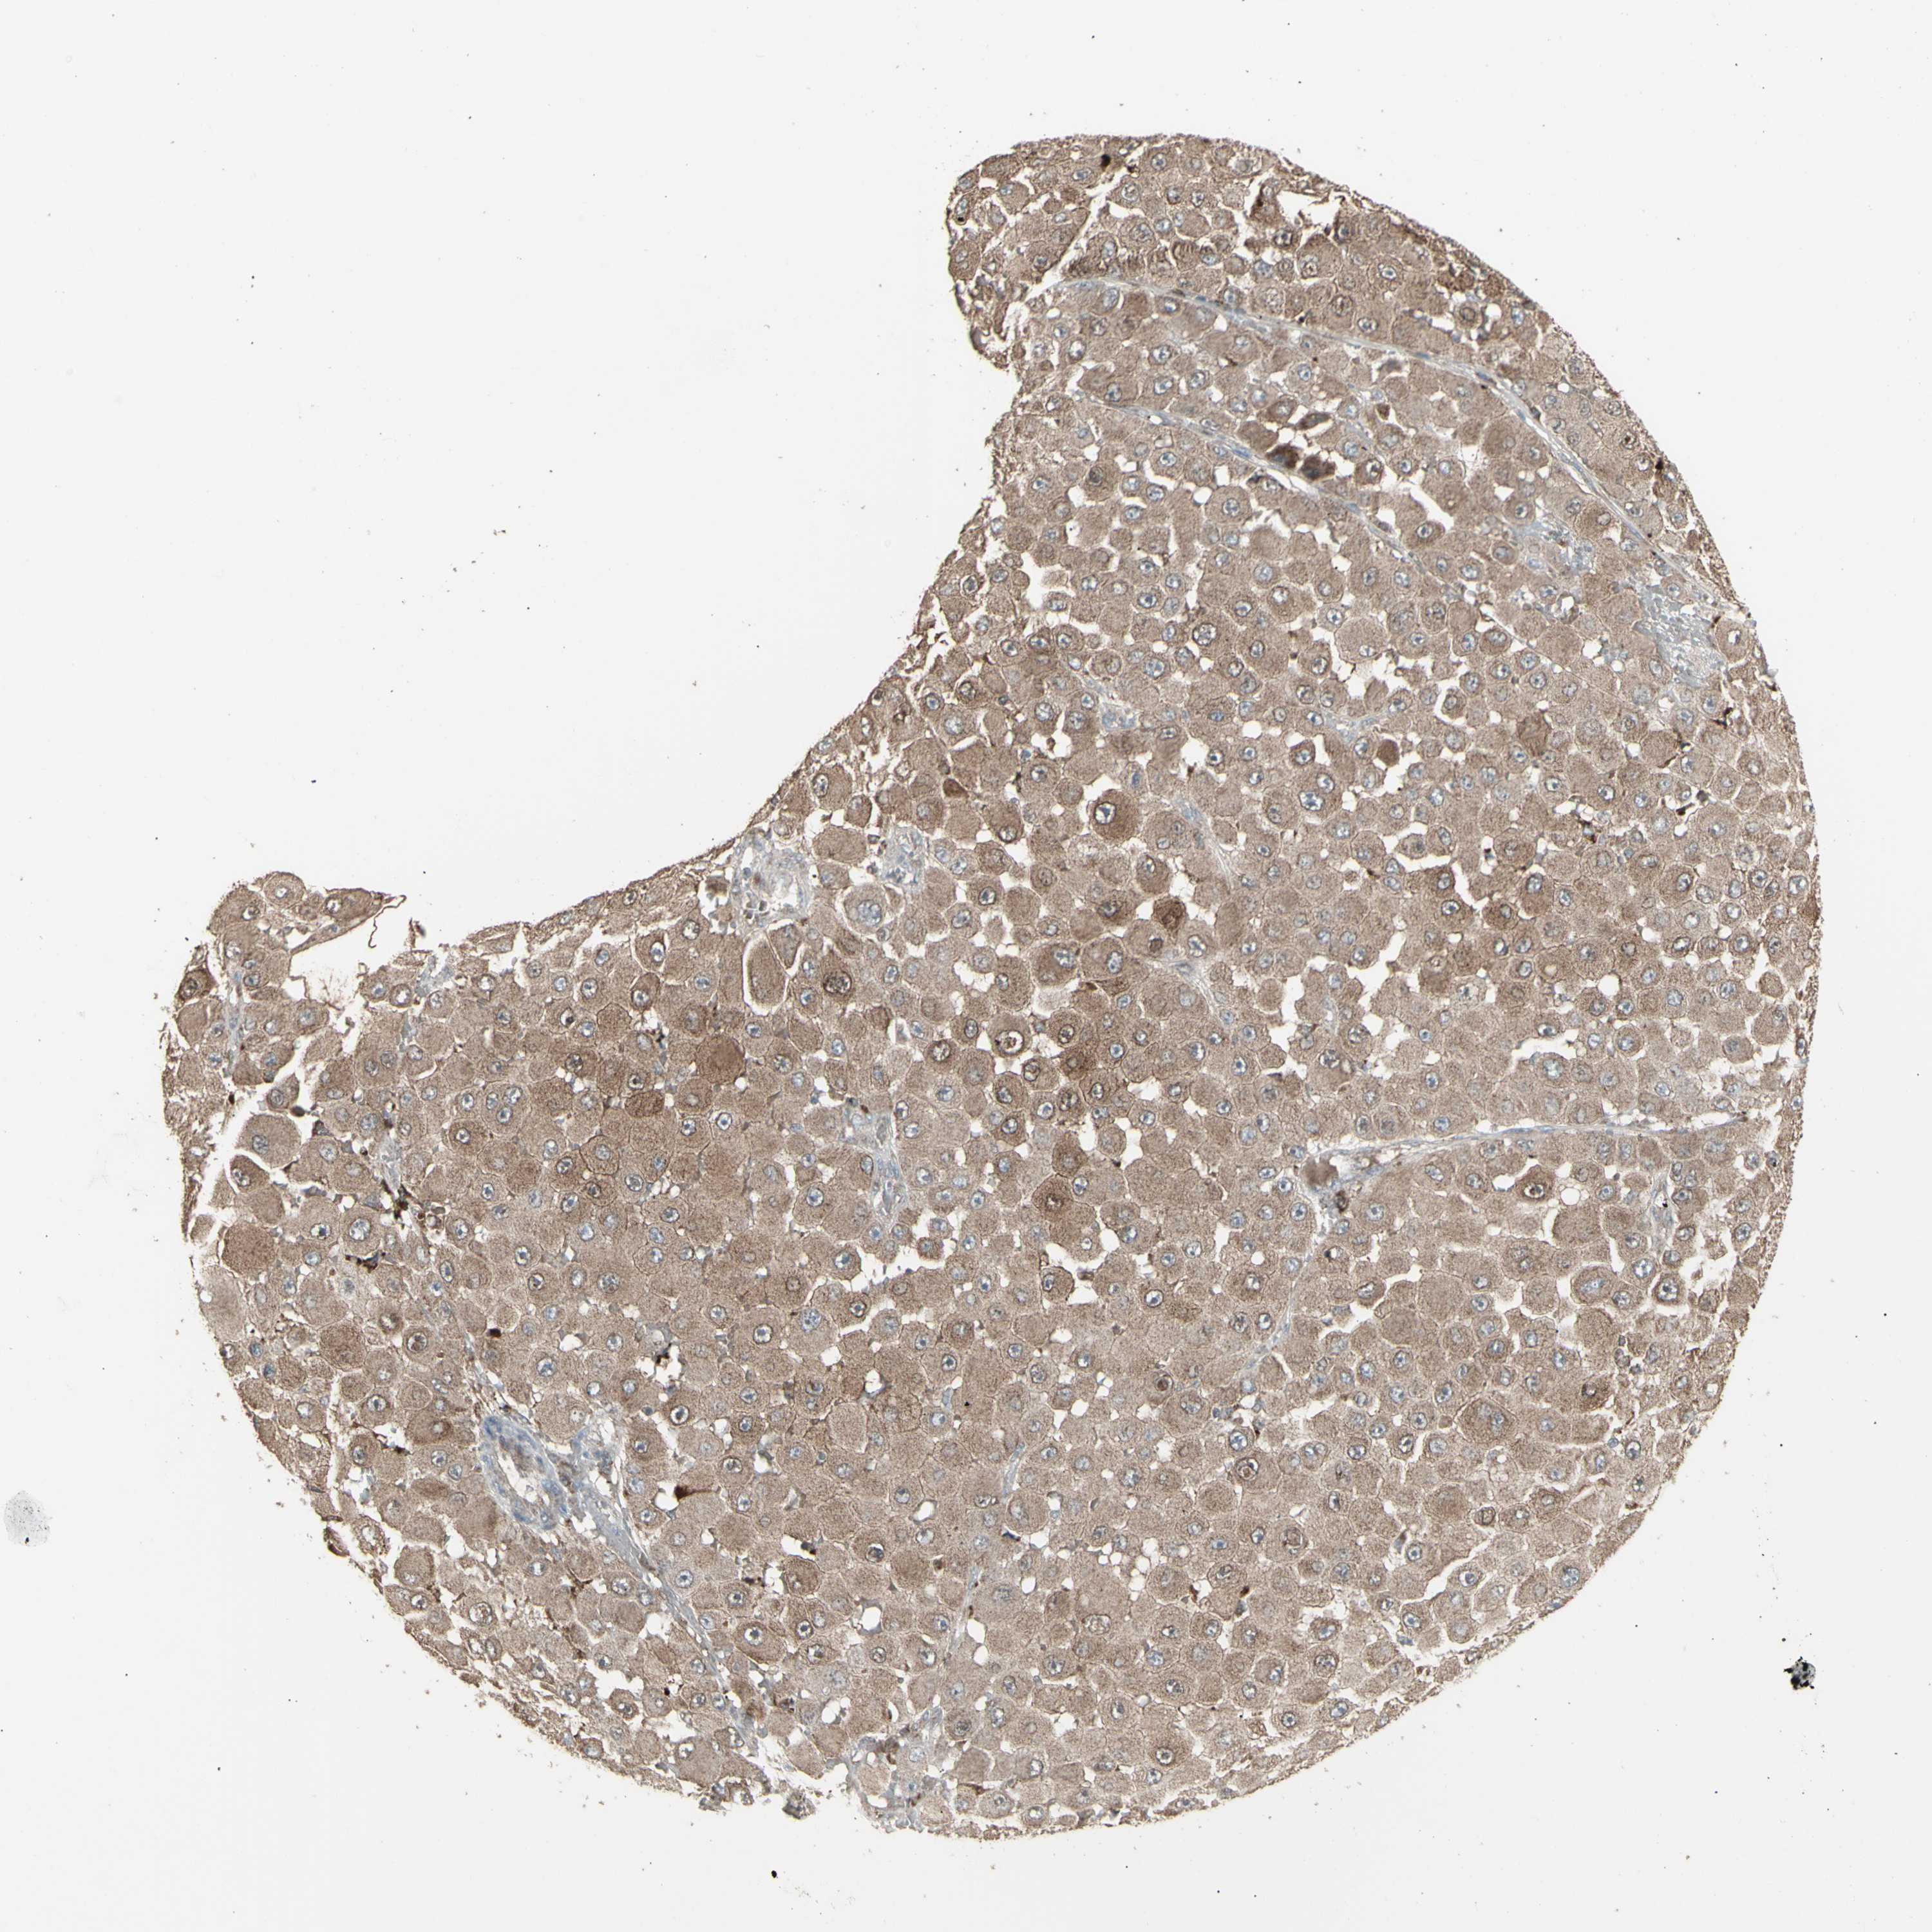

MELANOMA - Protein expressioni

A mouse-over function shows sample information and annotation data. Click on an image to view it in a full screen mode. Samples can be filtered based on level of antibody staining by selecting one or several of the following categories: high, medium, low and not detected. The assay and annotation is described here.

Note that samples used for immunohistochemistry by the Human Protein Atlas do not correspond to samples in the TCGA dataset.

Antibody stainingi

Antibody staining in the annotated cell types in the current human tissue is reported as not detected, low, medium, or high, based on conventional immunohistochemistry profiling in selected tissues. This score is based on the combination of the staining intensity and fraction of stained cells.

Each image is clickable and will lead to virtual microscopy that enables deeper exploration of all samples and also displays staining intensity scores, fraction scores and subcellular localization as well as patient and tissue information for each sample.

Antibody HPA002633

Antibody HPA046758

Antibody CAB010906

Staining

High

Medium

Low

Not detected

Intensity

Strong

Moderate

Weak

Negative

Quantity

>75%

75%-25%

<25%

None

Location

Nuclear

Cytoplasmic/membranous

Cytoplasmic/membranous,nuclear

Malignant melanoma, NOS

Malignant melanoma, Metastatic site

Malignant melanoma in situ